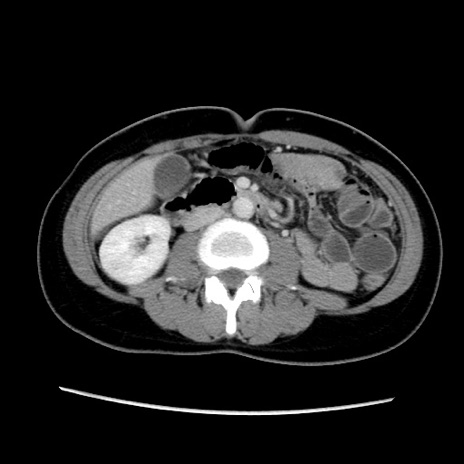

症例39(横断像)

【症例】40歳代女性

【主訴】上下腹部痛

【現病歴】2日目から下腹部痛あり。夜間は痛みで眠れなかった。昨日より上腹部痛と下痢が出現。臥位で痛みは軽快したため、休んでいた。本日になって臥位でも立位でも痛みが強くなってきたため救急要請。

【既往歴】子宮内膜症

【身体所見】部:平坦・軟、左上下腹部に圧痛あり、反跳痛あり。

【データ】WBC 21800、CRP 26.78